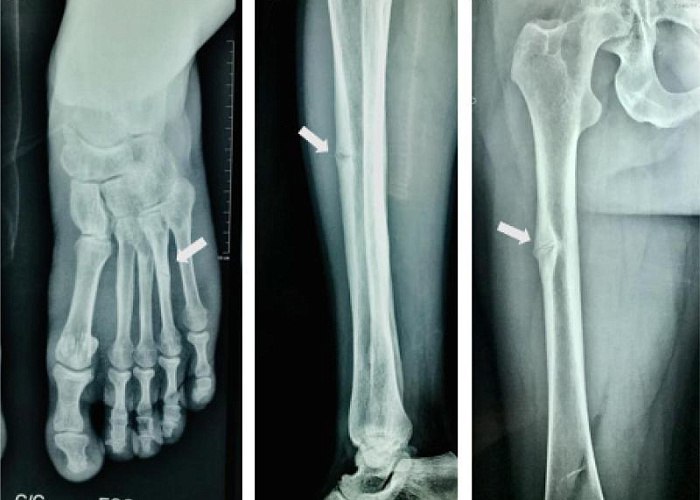

– К моему удивлению, никто из врачей не заметил снижение щелочной фосфатазы, неоднократно выявленной при анализах. Просто продолжали реабилитацию, – подметила врач-генетик ЧОДКБ Алена Побединская. – Это может сигнализировать о возможной наследственной гипофосфатазии.

Это генетическое заболевание часто вызывает выпадение зубов, ломкость костей, а также ухудшение памяти и почечную недостаточность.